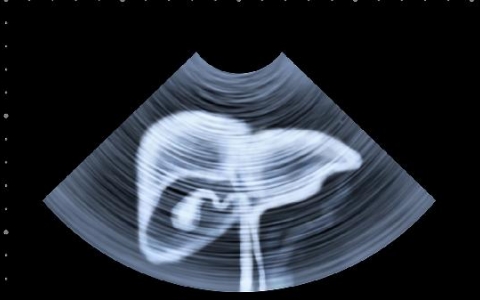

怎样判断是不是肝疼

可以通过医生查体、腹部检查、超声检查、计算机断层扫描、磁共振成像检查等方式判断是不是肝疼,采取检查时,需要去正规的医疗机构。1、医生查体:主要是检查皮肤黏膜颜色